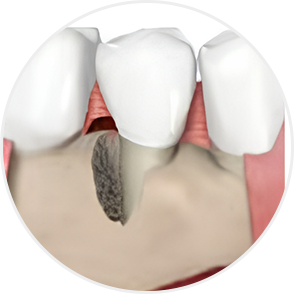

치주질환이란?

‘잇몸병’이라고 불리는 치주염은

잇몸과 잇몸뼈(치조골)를 파괴하는 대표적인 질환입니다.

초기에 단순히 잇몸이 붓고

피가 나는 수준에서 시작하지만,

방치하면 치조골이 점차 흡수되어

결국 치아를 발치해야 하는 상황까지 이어질 수 있습니다.

중기~만성 치주염

치아가 흔들리고 잇몸이 내려가 뿌리가 드러남